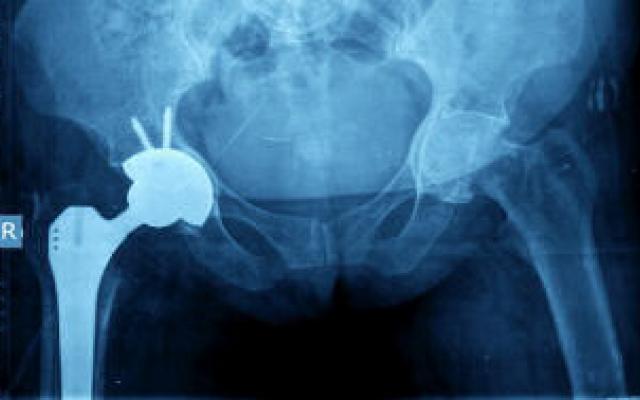

Lang niet iedereen die na een fractuur een totale heupprothese zou moeten krijgen, krijgt die ook. Volgens NICE-richtlijnen uit 2011 zouden patiënten met een gedislokeerde intracapsulaire heupfractuur een totale heup (THP: kop + steel + acetabulum) moeten krijgen, en niet alleen een nieuwe kop, als ze vóór hun ongeluk met…